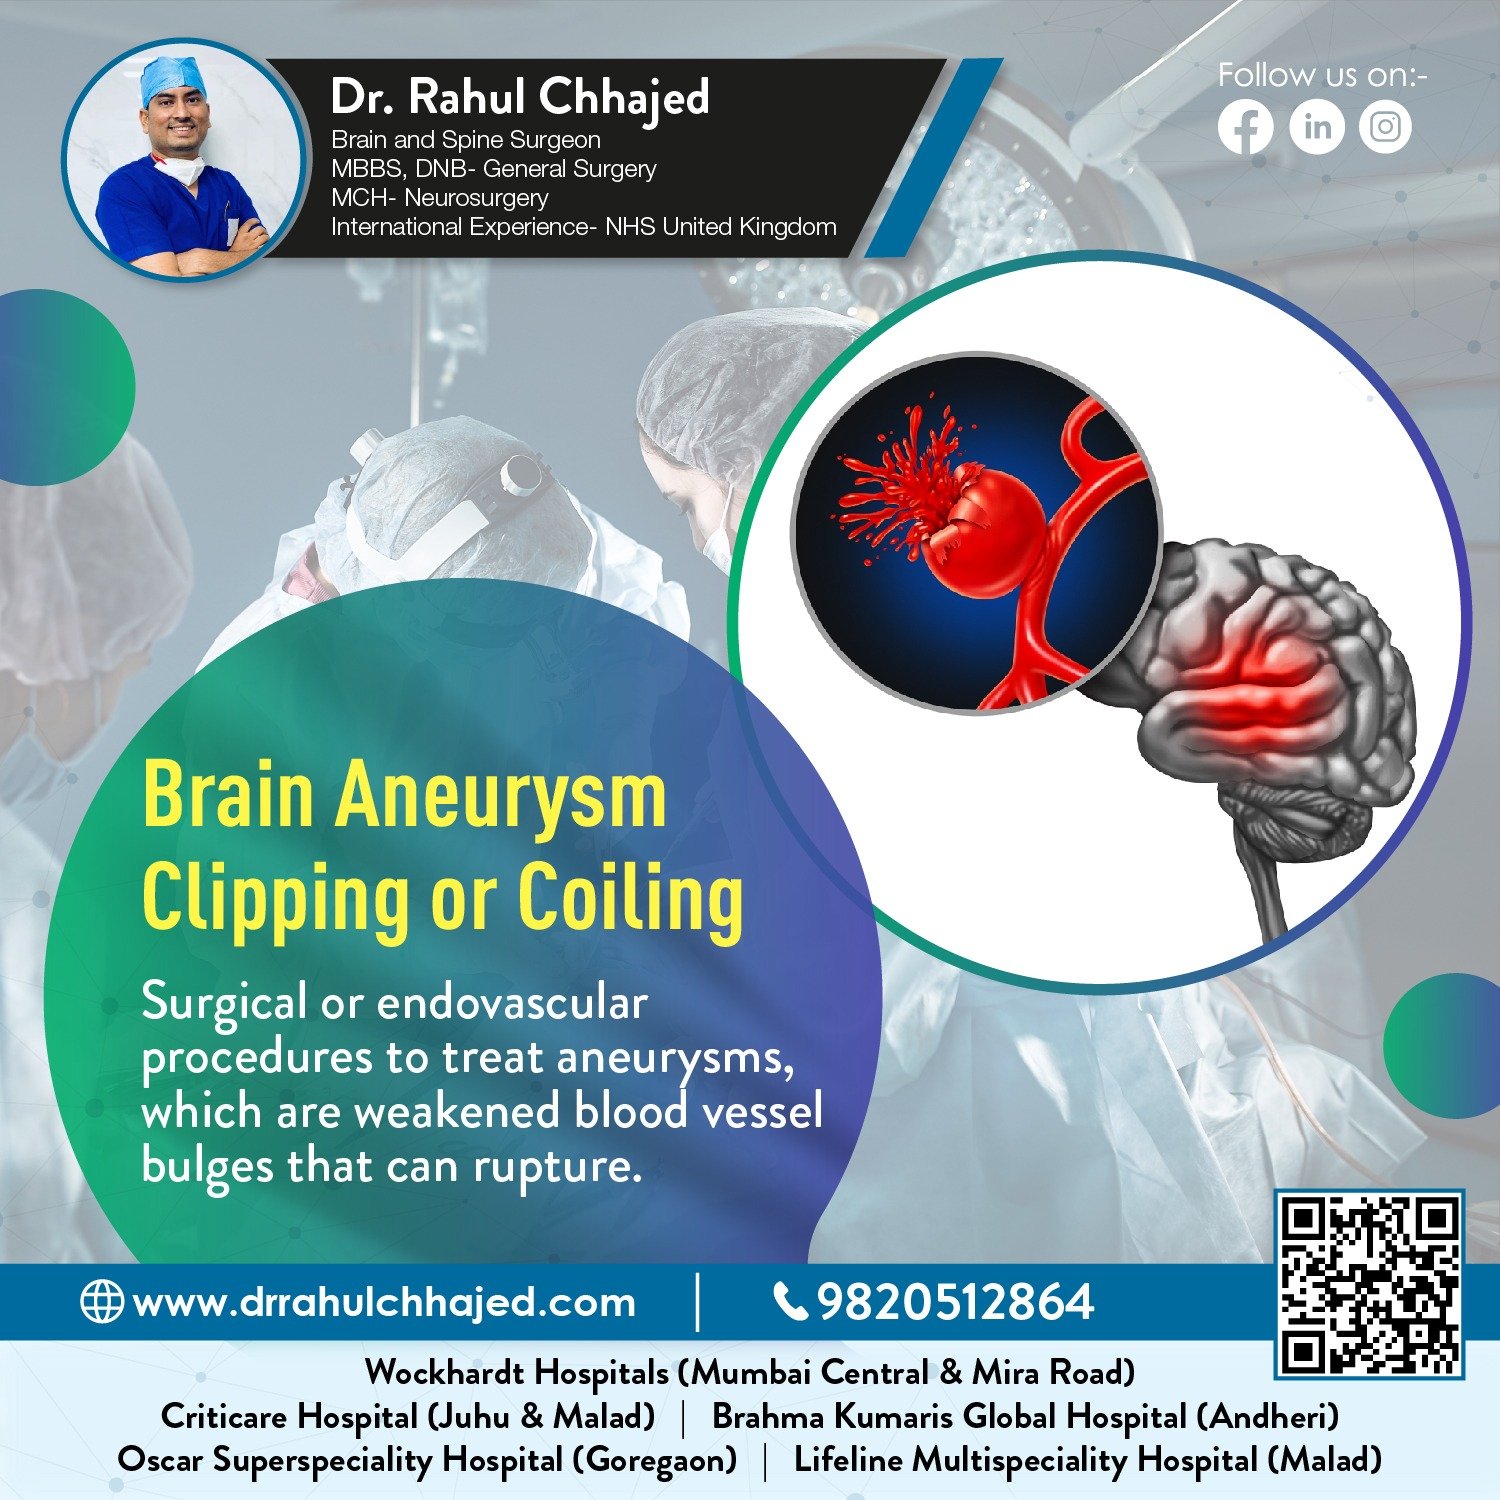

Brain Haemorrhage

A brain haemorrhage is caused by an artery in the brain bursting and causing localized bleeding in the surrounding tissues. We provide a comprehensive range of treatment options for brain hemorrhages, including surgical and non-surgical interventions.

A stroke is a medical emergency. We use the latest techniques and technologies to provide the highest quality stroke care, including clot-busting medications, minimally invasive procedures, and advanced rehabilitation programs.